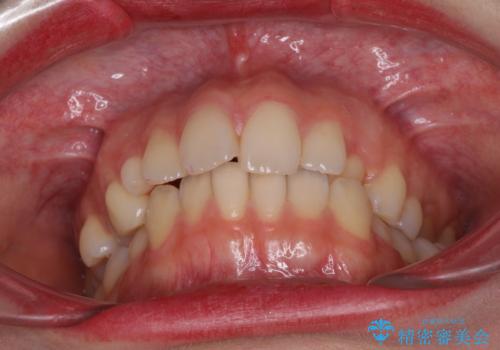

- 前歯のクロスバイトや残存している乳歯を気にして来院された患者様です。

上顎骨の幅が下顎骨よりも小さいので、拡大装置により骨幅を広げて上下関係を改善し、その後インビザラインにて歯並びを整えることとしました。